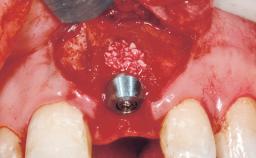

Late Flapless Placement of an Implant in a Maxillary Left Central Incisor Site

Type of Implants One-Piece

Bone Augmentation Horizontal|Staged

Augmentation Materials Xenogenous|Membrane

Bone Volume Deficient horizontally, requiring prior grafting